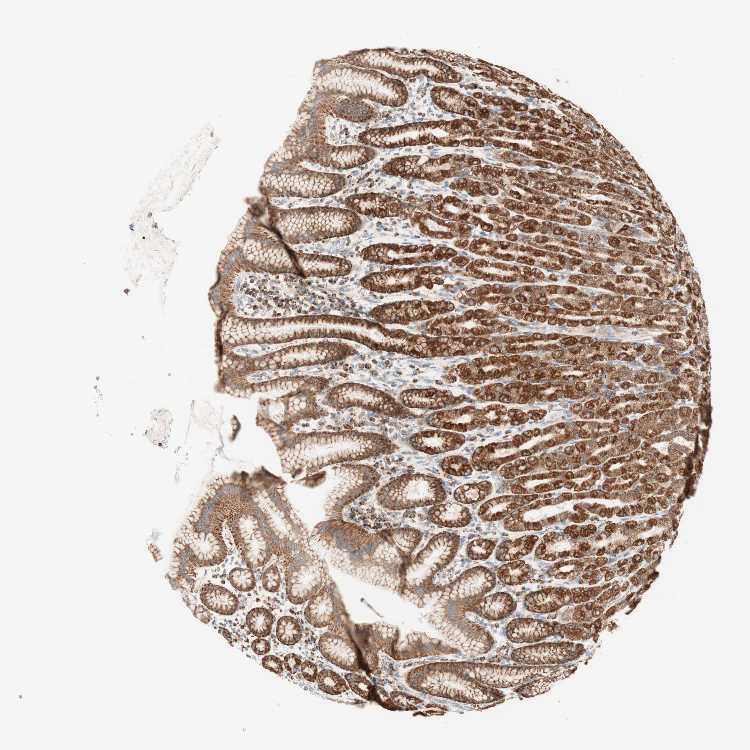

STOMACH 2 - Antibody stainingi

Antibody staining in the annotated cell types in the current human tissue is reported as not detected, low, medium, or high, based on conventional immunohistochemistry profiling in selected tissues. This score is based on the combination of the staining intensity and fraction of stained cells.

Each image is clickable and will lead to virtual microscopy that enables deeper exploration of all samples and also displays staining intensity scores, fraction scores and subcellular localization as well as patient and tissue information for each sample.

Antibody HPA011562Antibody CAB005585

Glandular cells HighHigh